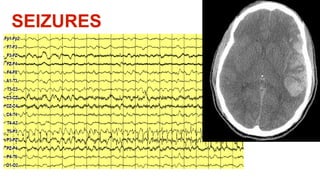

This document discusses using physiology as a target for treating traumatic brain injury (TBI). It summarizes key physiological parameters that should be monitored and targeted in TBI patients, including intracranial pressure (ICP), mean arterial pressure (MAP), partial pressure of brain tissue oxygen (PbtO2), cerebral blood flow (CBF), glucose levels, ventilation, and temperature. Maintaining these physiological markers within certain ranges can help optimize brain mechanics, metabolism and function for TBI patients.